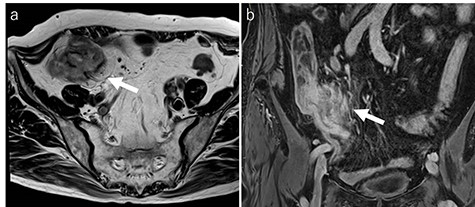

Laboratory tests revealed that her white blood cell count and carcinoembryonic antigen (CEA) levels were within normal limits (8600/μl and 2.4 ng/ml, respectively). However, C-reactive protein and carbohydrate antigen 19–9 (CA 19–9) levels were elevated (17.73 mg/dl and 87.8 U/ml, respectively). Colonoscopy showed swelling of the Bauhin valve and an elevated tumor of the terminal ileum (Fig. 1), but the biopsy specimen showed no malignancy. Abdominal contrast-enhanced CT detected a partially high-density tumor (diameter: 90 × 70 mm) in the cecum with some peripheral lymphadenopathy (Fig. 2). Magnetic resonance imaging (MRI) revealed a tumor (diameter: 60 × 40 mm) with thickening of the appendix wall near the cecum (Fig. 3). Although her pain resolved with conservative therapy, we diagnosed as suspected cecal cancer based on the imaging findings and elevated tumor marker levels.

MRI findings (a: T2-weighted axial image; b: contrast enhanced T1-weighed coronal image). MRI showing a tumor (diameter: 60 × 40 mm) with thickening of the appendix wall near the cecum (arrow).